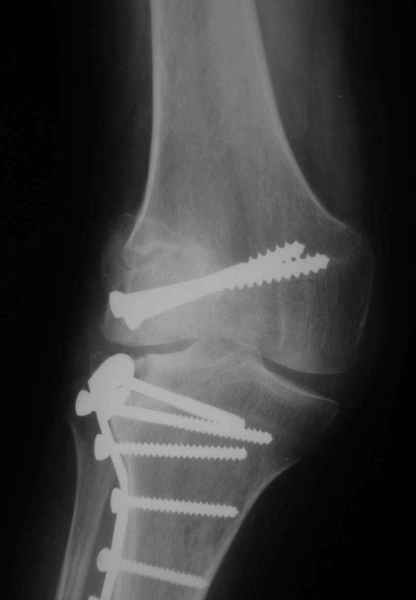

Как вариант решения прогрессирующей вальгусной деформации коленного сустава я бы предложил косую остеотомию дистального отдела бедра с фиксацией пластиной и компрессирующим винтом.

Взгляните на снимки , может быть это вам поможет.

Около 5 лет применяю этот тип дистальной остеотомии бедра для коррекции механической оси Н/К ( более 20 случаев) - достаточно эффективная операция.

Может стоит сначала добиться сращения наружного мыщелка бедра( костная пластика) и коррекции оси?

Мне представляется, что прогрессирующий вальгус и обусловлен несросшимся переломом мыщелка бедра (томограммы -зона межфрагментарного склерозирования), а циклические нагрузки на сустав во время ходьбы усугубляют ситуацию. Как вы думаете, в этой ситуации насколько вероятен риск развития аваскулярного некроза мыщелка бедра?

- Конечно, другая: я применял этот тип остеотомии при различных состояниях, приводящих к деформации механической оси сустава, но техника её тандартна,

расчеты индивидуальные.

-Деформация оси сустава может быть варусной или вальгусной, причины - структурные изменения в латеральном -или медиальном отделе сустава (переломы, патология зон роста, дисплазии, дегенеративные процессы) результат лечения внутри- или внесуставного перелома и восстановление оси обуславливается анатомичностью репозиции и адекватностью фиксации. Нередко в запущенных -неправильно срасшихся unicompartmental внутрисуставных переломах восстановление оси и опороспособности достигается периартикулярными

остеотомиями...